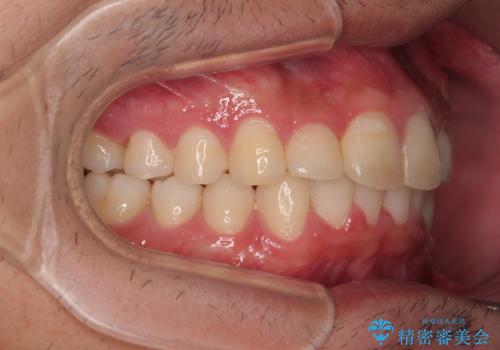

デコボコをインビザライン矯正で改善 奥歯は補助装置で確実に移動を

- ディープバイトと上顎前歯の突出、奥歯の咬み合わせを気にして来院された患者様です。

上顎歯列は全体的に前方位にあり、それが原因で深い咬み合わせとなり、突き上げにより上顎前歯が前方に飛び出している状態でした。

イメージしたとおりの仕上がりとなりました。